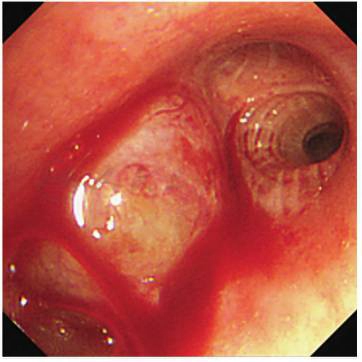

常规支气管镜检查:镜下见右肺上叶管口新生物,触之易出血;病灶予以活检(图2)。

图2 支气管镜示:右肺上叶管口新生物,完全堵塞右肺上叶支气管,触之易出血,色白;右肺中间干通畅